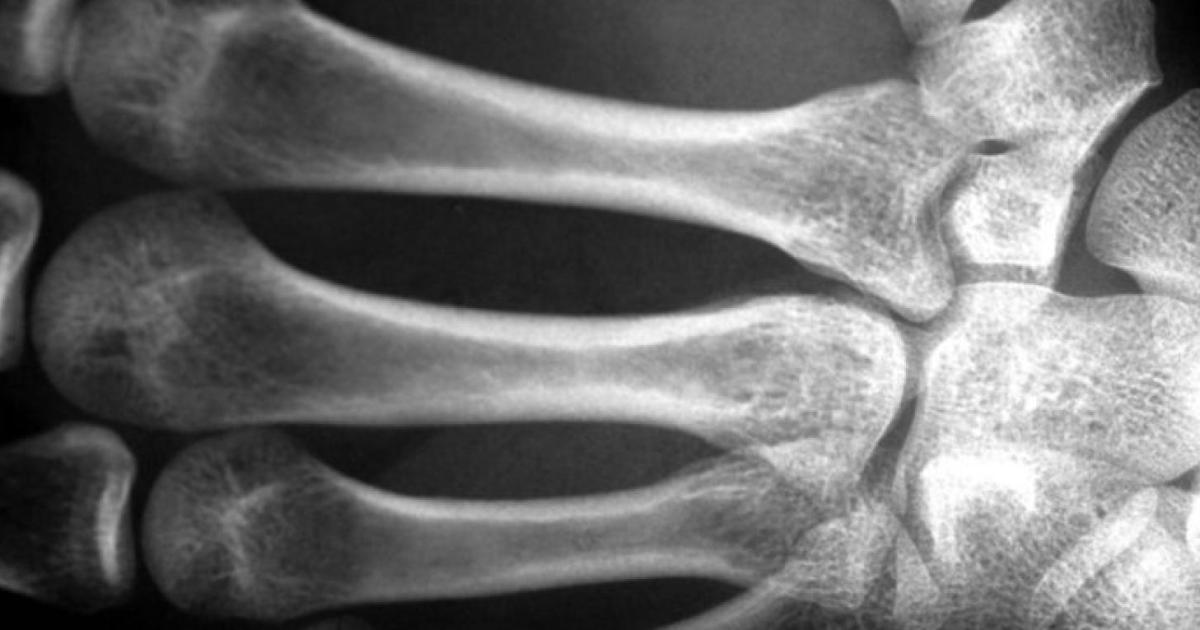

تقدّر المؤسسة الوطنية لصحة العمود الفقري في الولايات المتحدة أن مليوني رجل مصابون بهشاشة العظام، المرض الذي يعني أن تصبح العظام مسامية وتفقد تدريجيا كثافتها وقوتها، مما يعرّض الأفراد لخطر أكبر للإصابة بكسور العظام، حتى من السقوط البسيط.

ويعاني 16 مليون رجل من انخفاض كتلة العظام (osteopenia) وهي حالة تنخفض فيها كثافة المعادن في العظام عن القيم المرجعية الطبيعية، لكنها ليست منخفضة بما يكفي لتتوافق مع معايير تشخيص هشاشة العظام.